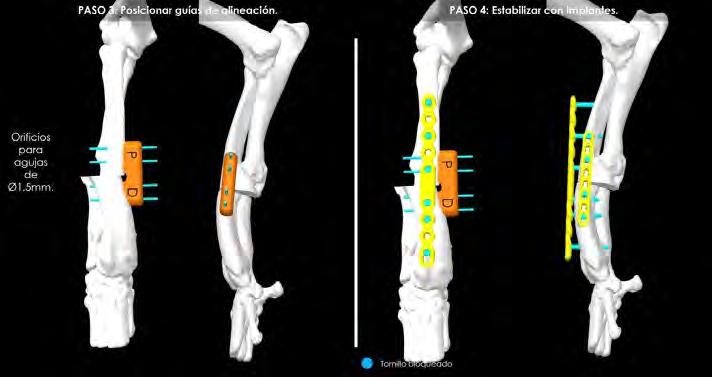

La planificación de la corrección angular se realizó apoyándonos en el estudio que, a partir de una segunda TC, hicieron los ingenieros de la empresa BETA Implants mediante la aplicación de la metodología CORA (Centro de Rotación de la Angulación) para:

1. determinar la deformación existente;

2. estimar la corrección que habría que realizar a partir de osteotomías asistidas por guías de corte y alineación hechas a medida para la paciente mediante impresión en 3D, usando una resina polimérica, biocompatible y esterilizable en autoclave;

3. y, por último, planificar la posterior estabilización del radio con placas bloqueadas.

En primer lugar, se llevó a cabo un estudio anatómico en el que se incluyeron tanto el radio derecho como el izquierdo. Esta metodología tiene como objetivo determinar el punto exacto (CORA) donde se debería efectuar el corte y la posterior corrección de la deformación ósea para conseguir su realineación fisiológica y biomecánica, mediante el uso de los ejes anatómicos y mecánicos, las líneas de orientación articular y los ángulos articulares.

Estas mediciones angulares nos permiten comparar el radio afectado con uno estándar y cuantificar cuánto se desvía de los valores morfológicos. Además, es clave realizar dichas mediciones también en la extremidad contralateral (Fig. 1), porque, en caso de no presentar ninguna patología o síntomas clínicos, nos permite aproximar la corrección y respetar en la medida de lo posible la distribución simétrica de cargas.3-5

Una vez realizadas estas mediciones, se puede determinar el CORA. La metodología que lleva por nombre este acrónimo se adaptó de la medicina humana y se aplicó al terreno de la veterinaria en 2006 para proporcionar un sistema de clasificación de deformidades angulares de las extremidades y una planificación preoperatoria, utilizando un vocabulario universal que puede aplicarse a cualquier deformidad de los huesos largos.3

Dicha metodología se basa en vistas ortogonales que muestran la posición de las articulaciones, ya que su orientación es el punto de partida para luego determinar la alineación de los huesos y las extremidades.

Las líneas que representan la orientación de las articulaciones, o líneas de orientación articular, se trazan a través de puntos de referencia anatómicos predefinidos. A continuación, se determinan los ejes óseos en

función de sus ángulos de intersección con las líneas de orientación articular, utilizando patrones de referencia o la propia extremidad contralateral, si no está afectada.

Si se elucidan más ejes de los que suelen existir para el hueso en cuestión, la intersección de los ejes óseos correspondería al vértice de la deformidad (o deformidades), lo que da lugar a la identificación de un CORA. Por ejemplo, el radio canino posee un eje anatómico singular en el plano frontal. Si se examina un radio concreto utilizando el método CORA y se establece que posee dos ejes anatómicos en el plano frontal que se cruzan dentro de las corticales del hueso, entonces la intersección de los ejes definiría una deformidad singular y se consideraría una deformidad uniapical.5 En nuestro caso, el CORA quedó determinado por la intersección de dos ejes anatómicos (líneas rosas en Figs. 1 y 2). Por tanto, en este punto es donde se realizará el corte y posterior giro del fragmento distal para realinear cúbito y radio, es decir, el punto donde se efectuará la ostectomía en estos huesos que al haber quedado unidos se tratarán en bloque (Fig. 2).

Tradicionalmente, la planificación de estas correcciones se realizaba sobre radiografías que servían de soporte para calcular y localizar el CORA. Sin embargo, la rectificación de la deformidad que se obtenía con esta metodología, usando tan solo radiografías, no ofrecía el mismo grado de rigor que con las propuestas actuales, ni permitía la corrección en todas las orienta-

ciones. Con el avance de la tecnología (incorporación de la TC) y la experiencia en el ámbito de la traumatología y ortopedia humana, empieza a tener relevancia

Figura 1. Comparativa en 3D de ambas extremidades con la correspondiente deformidad.

Figura 2. Simulación en 3D de la ostectomía correctiva que se ha de realizar según el software, una vez obtenido el CORA.

el empleo de guías quirúrgicas específicas. Estos dispositivos permiten reducir el tiempo de cirugía, aumentar la precisión (obteniendo mejores resultados) y disminuir errores en quirófano. Estas guías están diseñadas para encajar perfectamente sobre el hueso, puesto que se ha copiado la geometría de la TC, contando con dos ranuras para introducir la hoja de la sierra y realizar los cortes, con la orientación necesaria para obtener la corrección prevista (Fig. 3A).6,7 En este caso, se planificó la corrección para modificar la deformidad angular que sufrían cúbito y radio, adaptando lo más posible la anatomía de estos huesos a su conformación espacial deseable (en sus tres planos anatómicos: sagital, frontal y transverso), que en ocasiones es la del miembro contralateral, si en este no hay deformidad o es mínima.

Tras exponer el radio, el primer paso consistió en posicionar la guía de corte en la zona cráneo/medial del área media/distal de este hueso (según lo planificado), fijando temporalmente su posición con la ayuda de 4 agujas introducidas a través de los orificios proximales y distales de la guía. Una vez fijada, se realizaron los cortes con una sierra oscilante recta a través de las dos ranuras del dispositivo (Fig. 3B). A continuación, en un segundo paso, se retiró la guía de corte y se sustituyó por la de alineación, empleando el mismo sistema de fijación con agujas para conseguir la reducción de los fragmentos, según la planificación prevista. Esta segunda guía está diseñada para poder mantener en la posición adecuada los fragmentos mientras se estabilizan con la placa principal (Fig. 4A).

AB

Figura 3. (A) Reproducción en 3D de la aplicación de la guía quirúrgica que permitirá realizar los cortes adecuados sobre el cúbito y radio (ostectomía) posibilitando así la mejor alineación de estos huesos. (B). Imagen de la colocación de la guía quirúrgica durante la intervención.

Figura 4. (A) Reproducción en 3D de la aplicación de la guía de alineación para mantener la fijación de los huesos mientras se coloca la placa principal.

(B) Aspecto de la placa puente recién colocada junto a la guía de alineación.